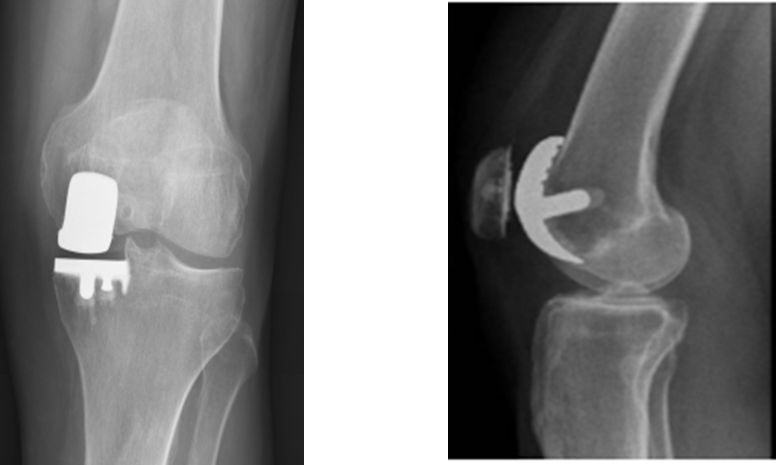

Thoái hoá khớp là hậu quả của quá trình cơ học và sinh học làm mất cân bằng giữa tổng hợp và huỷ hoại của sụn và xương dưới sụn.